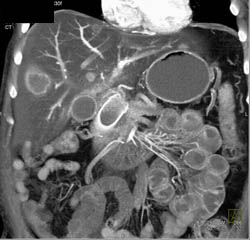

Cirrhosis With Varices